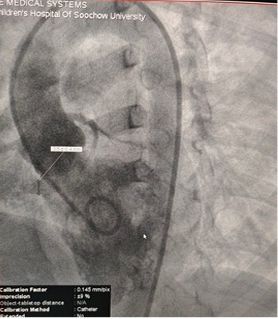

Präoperative Echo-Ergebnisse:

Basis durchmesser: ~ 6,1mm mit mehreren Austritts punkten

Membran artiges Gewebe über dem Defekt beobachtet

Farb doppler: Neben schluss fluss von links nach rechts

Diagnose: Peri membranous VSD

Selected MemoSorb ABFDQ-II 9 occluder based on intraoperative angiography and echocardiographic assessment.